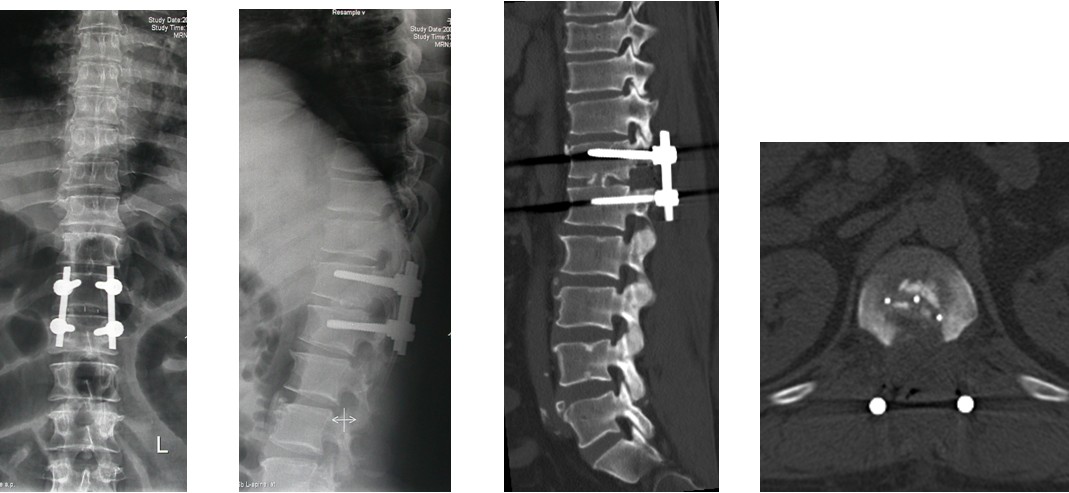

4. 典型病例:病例1,患者男性,40岁,司机。主因胸腰背部疼痛3年,肛周麻木、性功能减退并伴双足下垂2年,症状加重且二便肥力、无法工作1年入院。入院查体:一般情况良好,体胖、体重105kg。步态不稳,步行缓慢。胸腰段脊柱背部轻压痛,无放射。双侧股四头肌力IV级,双侧胫前肌力I级,双侧足下垂。鞍区感觉减退,无病理征。双侧跟、膝腱反射消失。血化验检查正常。X线平片显示T12~L1椎间隙明显变窄。CT显示T12~L1椎间盘突出并椎体后缘离断。MRI显示T12~L1椎间盘呈中央型突出,椎管狭窄,脊髓明显受压变形。入院诊断:T12~L1椎间盘突出症伴椎体后缘离断,马尾神经损害。术前检查完成后,在气管插管全麻下行上述经极外侧入路T12~L1椎间盘切除手术治疗,整个手术过程顺利,无术中及术后并发症发生,术后1周顺利出院。出院时,其双侧股四头肌、胫前肌肌力已分别恢复至V级和III级;鞍区感觉减退亦有明显好转。术后显示T12~L1突出之椎间盘及离断之椎体后缘已被完全切除,椎间融合器及椎弓根螺钉位置佳,脊柱局部生理曲度良好(图2a~2l)。病例2,女性患者,59岁。主因间歇性跛行,双下肢无力3年入院。入院诊断:T11椎体后上缘骨软骨瘤。以与病例1相同的术式行椎体骨软骨瘤的彻底切除(图3a~3l),无手术并发症发生,术后患者下肢症状明显改善。

图2a~2d. 典型病例1患者术前CT, MRI均显示为T12~L1椎间盘突出合并椎体后缘离断, 致椎管狭窄, 脊髓明显受压

图2i~2l. 典型病例1患者术后X线片, CT显示突出之椎间盘及离断的椎体后缘已被彻底切除, 内固定和椎替间融合器位置良好.